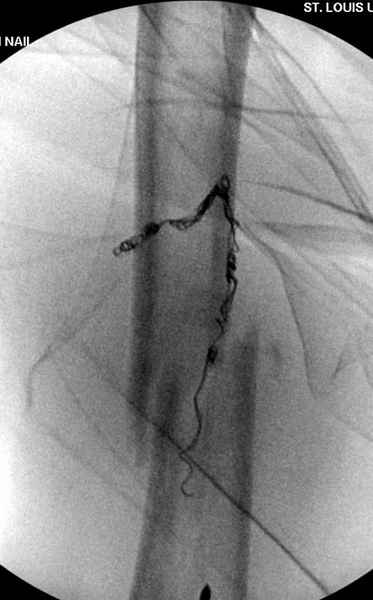

Для предупреждения кровотечения во время рассверливания, за день до операции провели эмболизацию сосудов питающий метастаз. http://radiology.rsnajnls.org/cgi/reprint/150/3/673.pdf (7-11, 12-15-16)

С минимальным рассверливанием и ретроградным методом провели остеосинтез бедра 12 мм гвоздем. (17-20)

Кровопотеря во время операции меньше 100 мл.